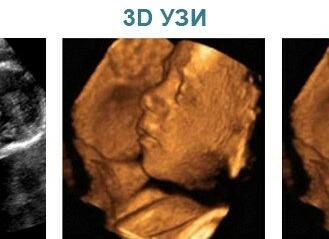

Для проведения ультразвукового исследования используется специальная аппаратура. Обследование у беременных проводится обычно с помощью трансвагинального или трансабдоминального датчиков. Полученное изображение отображается на мониторах.